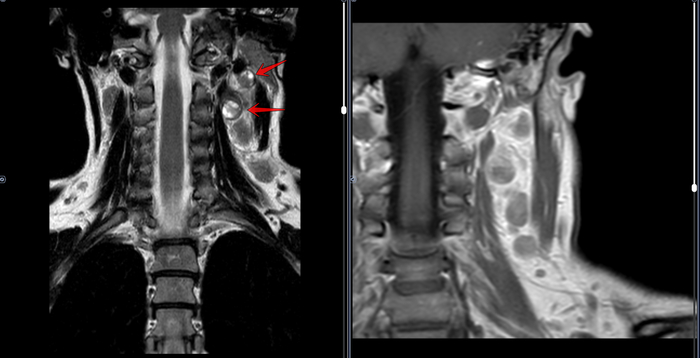

Изображения и частично текст взяли с радиопедии radiopaedia.org. 1 МРТ Т1, 2 МРТ Т2 (кейс 1), 3 - КТ с контрастом (кейс 2)

На что важно обращать внимание при описании КТ/МРТ у пациента с меланомой?

"Поражение опухолью следующих структур связано с плохим прогнозом или классифицируется как стадия Т4b (например, неоперабельность, ассоциированная с технической невозможностью получить чистые края резекции):

✔️значительное поражение крыловидно-небной ямки, тяжелые тризмы из-за инфильтрации опухолью крыловидных мышц;

✔️макроскопическое распространение опухоли на основание черепа (например, эрозия крыловидных пластинок или основной кости, расширение овального отверстия и др.);

✔️возможная инвазия (охват) стенки общей или внутренней сонной артерии. А вот сейчас внимание, что важно не упустить при описании❗ Охват обычно оценивается радиологически (по данным КТ и МРТ) и диагностируется, если опухоль окружает ≥270° окружности сонной артерии; непосредственное распространение опухоли из регионарных ЛУ с поражением кожи, прямое распространение на структуры средостения предпозвоночную фасцию или шейные позвонки.

Таким образом, для рентгенолога при описании КТ/МРТ у пациента с меланомой ключевое внимание должно быть сосредоточено на оценке инвазии в критические структы: основание черепа, крыловидно-небную ямку, сосуды (особенно сонные артерии) и нервы. Выявление периневральной инвазии или прорастания кости — это не просто констатация факта, а прямая подсказка для хирурга об объеме необходимого вмешательства. Пациенту с подозрением на меланому или с установленным диагнозом следует обращаться к дерматологу и онкологу. Лечащему врачу на основании данных визуализации необходимо четко планировать совместно с хирургом и радиологом возможность и целесообразность радикальной резекции, используя интраоперационное патогистологическое исследование для контроля краев резекции.